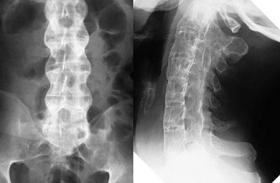

Nguyên nhân viêm cột sống dính khớp và cách chữa